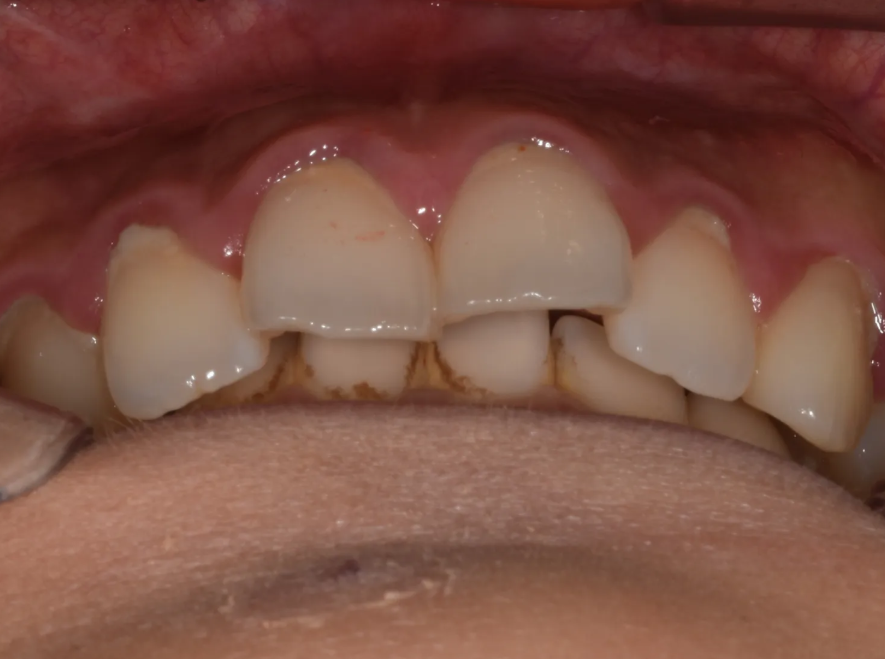

측면에서 보면 오버젯 문제가 조금 더 잘 보입니다

사실 이 환자분은 과거에 아래턱이 작다는 이유로 턱끝수술(턱끝을 앞으로 내미는 수술)을 받으신 적이 있었습니다. 참고로 환자분 같은 경우 윗니가 아랫니보다 훨씬 앞쪽에 위치하게 되므로, 상대적으로 턱이 들어가 보일 수 있습니다.

엑스레이를 보면 윗니(파랑)가 아랫입술(노랑)을 누르고 있습니다.

아랫니(빨강)은 보통 사람과 다르게 윗니의 (중간부분이 아닌) 뿌리와 닿아 있습니다.